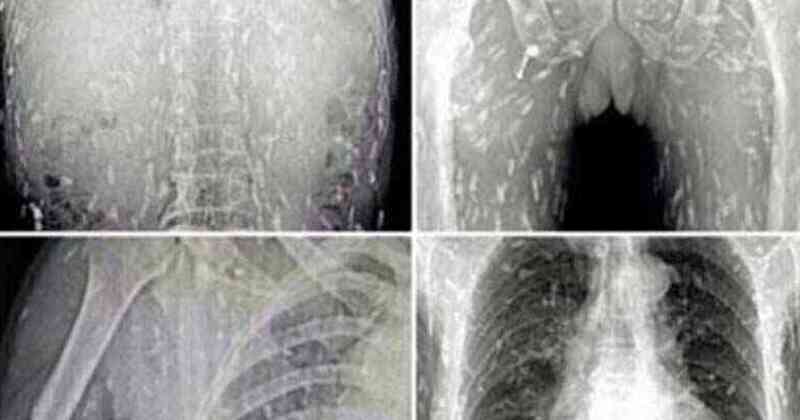

เว็บไซต์ข่าวมีร์เรอร์แชร์ภาพเอ็กซ์เรย์ชวนอึ้งของชายผู้รักการกินซูชิเป็นชีวิตจิตใจ ที่หารู้ไม่ว่าสิ่งที่ชื่นชอบกำลังทำให้ร่างกายของเขาถูกทำลาย หลังภาพเอ็กซ์เรย์ปรากฏว่าข้างในร่างกายเต็มไปด้วยพยาธิตัวตืด!

ชายชาวจีนผู้รักการกินซูชิรายหนึ่งมาพบแพทย์ หลังจากมีอาการปวดท้องและคันไปทั่วผิวหนัง และก็ต้องผงะ เมื่อภาพเอ็กซ์เรย์ที่ออกมาร่างกายของเขาเต็มไปด้วยพยาธิตัวตืด เป็นผลมาจากการกินซาซิมิมากเกินไป หลังจากเขาจับปลาในน้ำจืดมาแล่กินเองแบบดิบๆ

โดยแพทย์เชื่อว่าอาหารญี่ปุ่นประเภทเนื้อดิบและปลาดิบจะมีการปนเปื้อนสิ่งที่ไม่พึงประสงค์ที่ส่งผลให้มีการติดเชื้อปรสิตได้หลากหลายชนิด

พยาธิตัวตืด เกิดขึ้นจากการบริโภคเผลอไปบริโภคตัวอ่อนของพยาธิตัวตืดเข้าไป พบได้ในปลาที่อยู่ในแหล่งน้ำจืดเช่น แซลมอน (ซึ่งปกติเป็นปลาที่อยู่ในน้ำเค็มแต่จะมาวางไข่ในน้ำจืด) และมันสามารถอยู่รอดในร่างกายของมนุษย์ได้นานเป็นปี และวางไข่ทิ้งไว้ตามส่วนต่างๆของร่างกายและแพร่พันธุ์ได้อย่างรวดเร็ว

และอันตรายยิ่งเพิ่มขึ้นหากมันเคลื่อนตัวไปยังอวัยวะที่สำคัญจะดีกว่าถ้าเรากินอาหารที่ปรุงสุกแล้ว